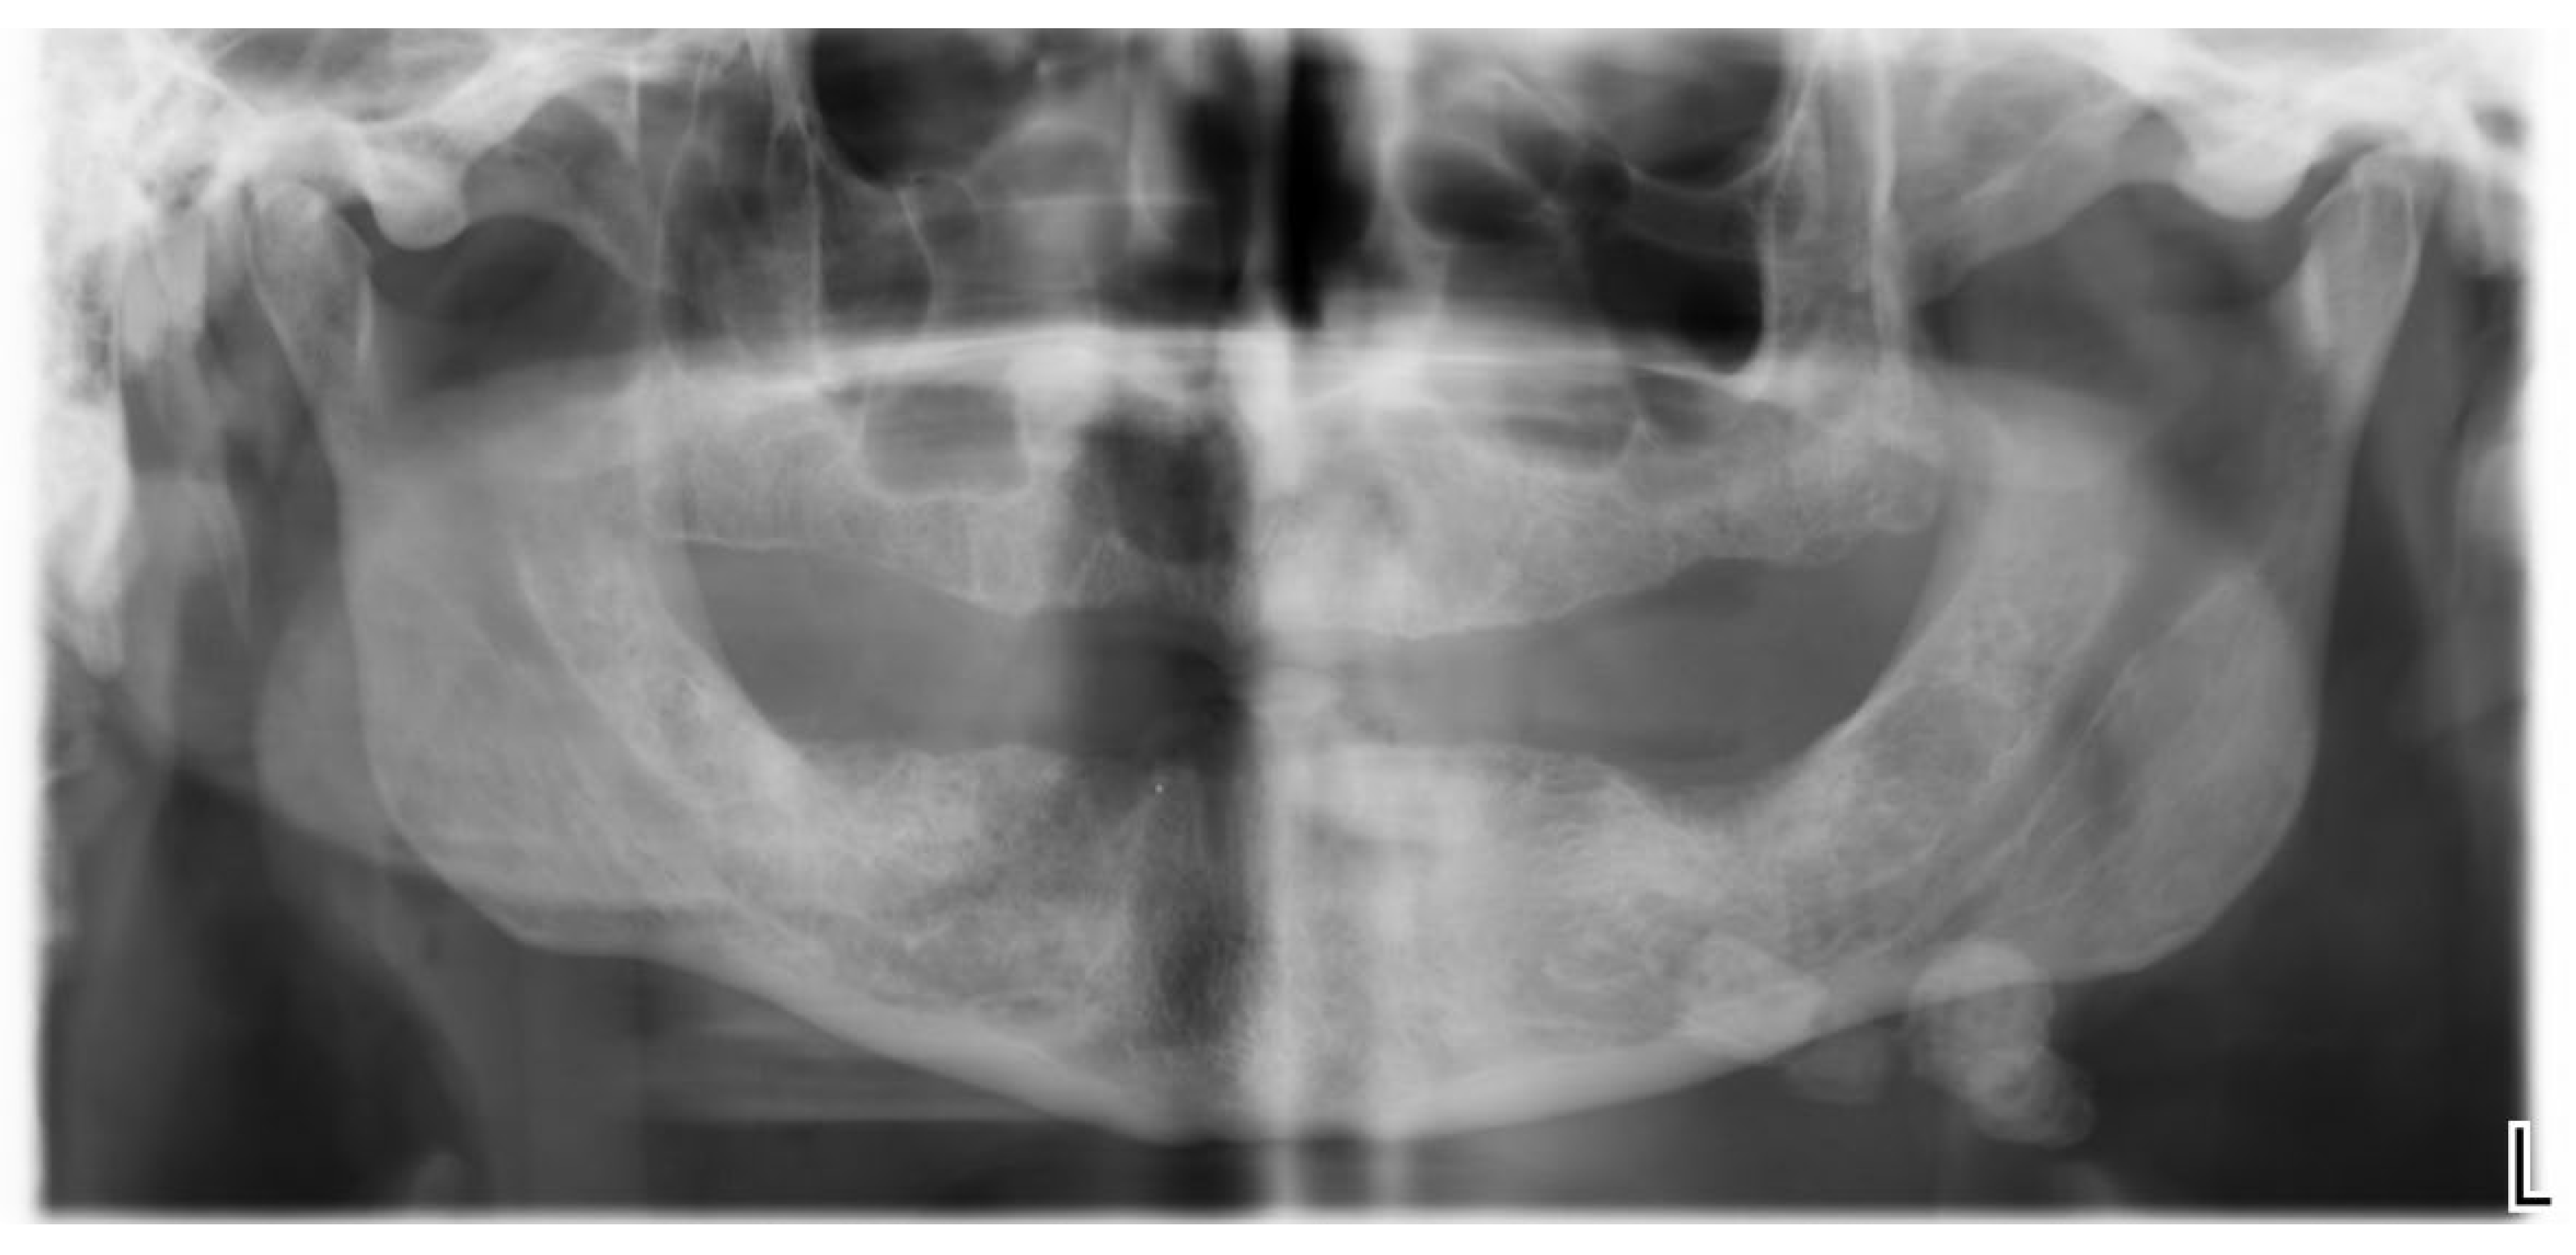

| Azaz et al. (1996) [18] | Case series | 49 cases, 26 M ,23W: (15Y-18Y) |

Wharton’s duct :47 Stensen duct: 2 |

CO2 laser | 1020 8W CW | Four patients had antibiotics for 5 days | Four patients experienced discomfort | 7 days after for the follow up. And after one years. | Excellent results with no bleeding, minimal scarring, and little discomfort. Sialadenectomy should be considered for patients who suffer from recurrent symptoms. |

| Barak et al. (1991) [19] | Case series | 21 cases, 14M, 7W. |

Wharton’s duct: 10 patients.Submandibular/sublingual glands:8 patients.Stensen duct: 3 patients. | Co2 laser | 5W/10W in continuous mode | - | No complication | Three weeks. | Complete healing after three weeks |